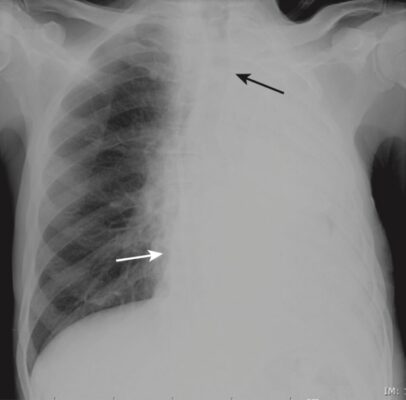

Tình huống: Anh S, 31 tuổi, đến khoa cấp cứu trong tình trạng khó thở cấp tính. Hình chụp X quang ngực thẳng của anh được thể hiện trong Hình 1.

- Như bạn có thể thấy, toàn bộ nửa phổi trái của anh S bị mờ.

- Trở lại ca bệnh (anh S) với hình chụp X-quang phổi thẳng có mờ nửa phổi trái. Bất thường ở đây là gì?

- Hình ảnh cho thấy có sự dịch chuyển của tim và khí quản về phía phổi bị mờ (Hình 9). Đây là đặc điểm của xẹp toàn bộ một phổi. Do độ tuổi (31) và tiền sử mắc bệnh hen (bạn đã hỏi về bệnh sử), rất có thể là biểu hiện xẹp phổi do một nút chất nhầy gây tắc nghẽn.

- Anh S đã được chụp CT, cho thấy tắc nghẽn ở phế quản chính bên trái và nút nhầy sau đó đã được lấy ra bằng nội soi phế quản.